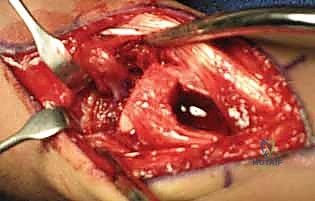

يقوم الدكتور هطيف بعمل شق جراحي دقيق متعرج أو مستقيم على ظهر الرسغ (Dorsal Approach) فوق العظم الزورقي وعظم الكعبرة. يتم إبعاد الأوتار الباسطة بعناية فائقة لحماية الأعصاب والأوتار المحيطة.

3. تحديد الشريان المغذي (The 1,2 ICSRA)

باستخدام النظارات المكبرة الجراحية (Loupes) أو الميكروسكوب الجراحي، يقوم الدكتور هطيف بالبحث عن الشريان الدقيق (1,2 ICSRA) الذي يمر بين الحيز الأول والثاني للأوتار الباسطة. يتم عزل هذا الشريان مع شريط صغير من الأنسجة المحيطة به لحمايته وضمان استمرار تدفق الدم فيه.

4. استخراج الطعم العظمي الوعائي (Harvesting the Graft)

بمجرد تأمين الشريان، يتم استخدام منشار عظمي دقيق جداً لقطع كتلة عظمية صغيرة من ظهر عظم الكعبرة، بحيث يظل الشريان متصلاً بها بإحكام. الآن أصبح لدى الجراح قطعة عظمية "حية" وجاهزة للنقل.

5. تحضير العظم الزورقي (Debridement)

يتم فتح كبسولة مفصل الرسغ للوصول إلى العظم الزورقي المكسور. يقوم الدكتور هطيف بتنظيف منطقة عدم الالتحام بالكامل، وإزالة كل الأنسجة الليفية، والتكيسات، والعظام الميتة (النخرية) باستخدام أدوات دقيقة (Curettes) ومثاقب صغيرة، حتى يصل إلى حواف عظمية صحية تنزف دماً (علامة على الحيوية). هذا يترك فجوة بحاجة إلى الحشو.